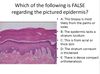

Q

Question 1

Question 2

Question 4